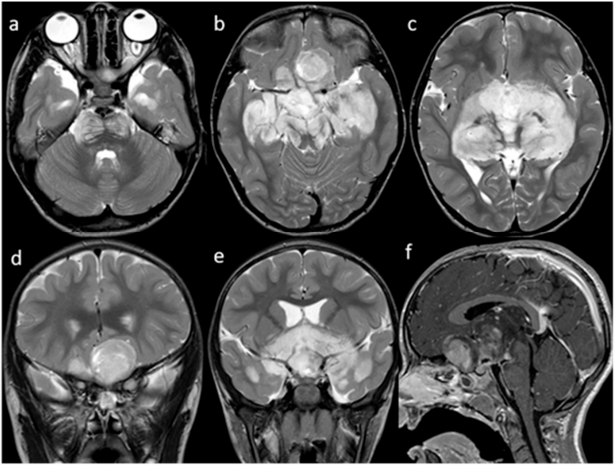

大脑和脊髓的磁共振成像(MRI)记录了涉及视交叉区的浸润性占位病变(图1)。

图1. 核磁共振成像。T2w轴位(a–c)和冠状位(d,e)图像显示一个大的、不均匀的高强度视交叉分叶状肿块,累及视神经和视束、视辐射、下丘脑、颞叶和脑干。肿块压迫额叶并延伸至第三脑室,导致侧脑室适度扩大。矢状位Gd T1w(f)图像显示鞍上肿块的不均匀对比增强。